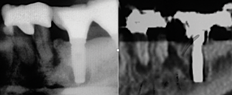

Over the past 30 years, multiple robust experimental and clinical studies have proven Bränemark's osseointegration principle of titanium dental implants. However, their widespread use has resulted in numerous types of complications. Even when the most stringent rules for sterility are followed, optimal surgical planning is carried out, and careful patient selection/preparation is practiced, some implants will fail in either their integration or prosthetic phase. An implant periapical lesion is a rare complication that may occur following implant placement, and case reports have suggested that such lesions are a possible reason for early failure of an endosseous implant.1-3 Ailing and failing implants can be treated to try to preserve them; however, failed implants must be removed because they are nonfunctional and bone loss will continue. The apical lesion described in this article is considered to be a different category, as typical pocket pathology is unrelated to this condition (Figure 1).

Fig 1. Crestal (left) versus apical (right) peri-implantitis.

Figure 1